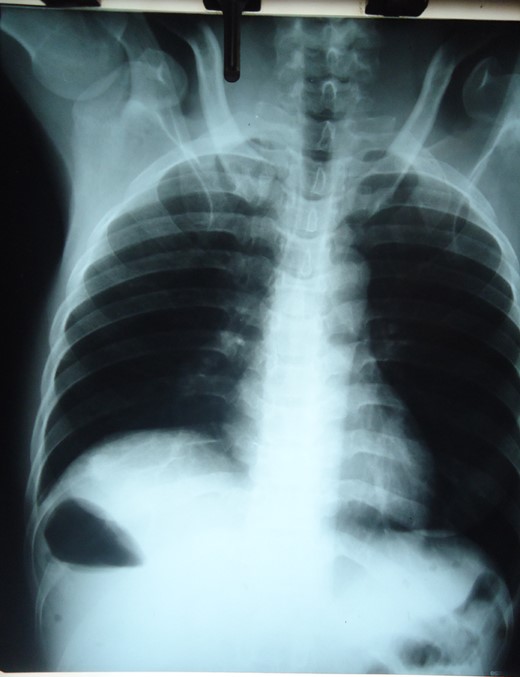

Chest X-ray showing right sub-diaphragmatic shadow with air fluid levels from trapped bowel.

Small intestinal volvulus presents with severe colicky abdominal pains and vomiting that is difficult to differentiate from non-strangulating causes of intestinal obstruction. Early diagnosis and operative intervention is important to prevent gangrene seen in more than 40% of cases [3]. Mortality rates of 5.8–8% increases to 20–100% with gangrene [7]. Abdominal CT especially Multidetector CT with angiography is the most specific investigation [8]. Doppler ultrasonography showing the whirlpool sign is useful but operator dependent [9]. Plain radiography is insensitive in most cases. The plain radiographs of our patient showed a significant gas shadow below the right hemi-diaphragm that was discovered to be from entrapped bowel between the liver and diaphragm. An abdominal CT though more specific was omitted to minimize delay in the management. Radiological sign of hepato-diaphragmatic interposition of bowel loops was first described by Demitrus Chilaiditi in 1910 but the appearance in this patient differs from previous descriptions. Cases of Chilaiditi's syndrome have been reported in association with Fitz-Hugh-Curtis syndrome in large intestinal obstruction but none with small intestinal volvulus [10]. Treatment of small intestinal volvulus is derotation of the affected loop when viable and resection of gangrenous segments. Associated anatomical abnormalities are corrected by closure of intra-peritoneal defects, adhesiolysis or excision of mass lesions.